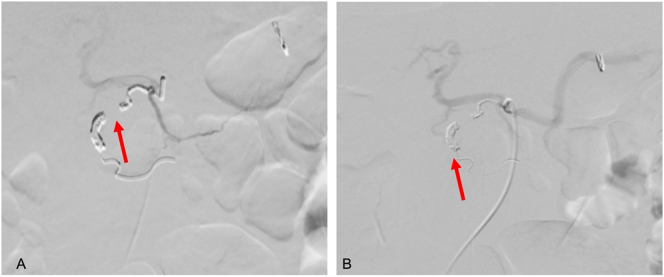

Due to the persistence of melaena and rectal bleeding associated with new upper gastrointestinal bleeding, a new EGDE was requested with evidence of active layered bleeding in gastric ulcers. Hemostasis was performed with hemoclip. Selective arteriography was performed, where an abrupt interruption of the gastroduodenal artery was found in relation to the pancreatic mass confirming a pseudoaneurysm (Fig. 2). As well, initial suspicion of rupture of the pseudoaneurysm into the duodenum was ruled out according to the arteriography, and for that reason the preferred management was an endovascular coil embolization, which was performed, achieving distal occlusion of the vessel, with no evidence of persisting bleeding on inspection (Fig. 3).

Fig. 3.

A. Embolization of gastroduodenal artery pseudoaneurysm (red arrow pointing vessel tract). B. Confirmation of coil positioning (red arrow pointing coil).